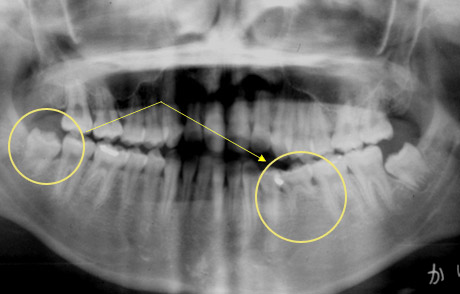

17歳、少女。左下の第二小臼歯が生まれつきありません。そこで、右下親知らずの移植を行いました。この症例では、左下の親知らずでもドナー歯として大丈夫ですが、抜歯しやすい右下を選びました。